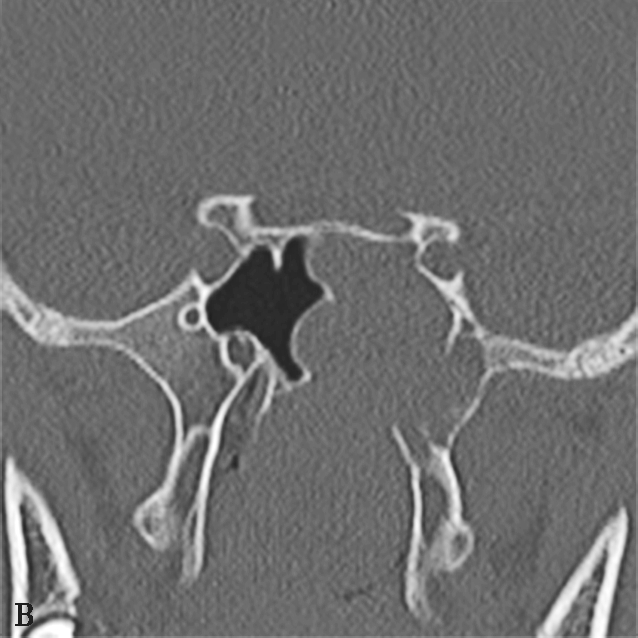

图1-2-5 青少年非角化型鼻咽癌

患者男,14岁,反复间断鼻出血、头晕头痛20余天。A.鼻窦CT横断面骨窗,示鼻咽顶后壁左侧软组织肿块,累及后鼻孔区,邻近左侧岩尖、蝶骨翼突骨质破坏、不完整,边缘毛糙;B.鼻窦CT冠状面重组骨窗,示左侧鼻咽顶后壁软组织肿块,邻近蝶骨翼突溶骨性骨质破坏,累及蝶骨体,边缘毛糙不整;C.鼻咽部MR T 2 WI横断面,示鼻咽左侧壁软组织肿块呈不均匀稍高信号,其间可见条状高信号,未见血管流空影;病变累及左侧翼内肌、窦后脂肪间隙;左侧上颌窦内可见积液呈明显高信号;D.鼻咽部MR T 1 WI横断面,示鼻咽部软组织肿块呈等信号,左侧上颌窦内积液呈低信号;E.鼻咽部MR T 1 WI横断面增强脂肪抑制序列,示鼻咽部病变呈明显强化,累及鼻咽左侧壁、顶后壁并跨越中线累及右侧咽隐窝,右侧咽后间隙淋巴结可见,与软组织肿块同步强化;F.鼻咽部MR T 1 WI冠状面增强脂肪抑制序列,示病变累及左侧咽旁间隙,左侧上颌神经明显增粗强化,并经上颌神经累及左侧海绵窦致其增厚、强化。活检病理符合鼻咽癌(非角化型)